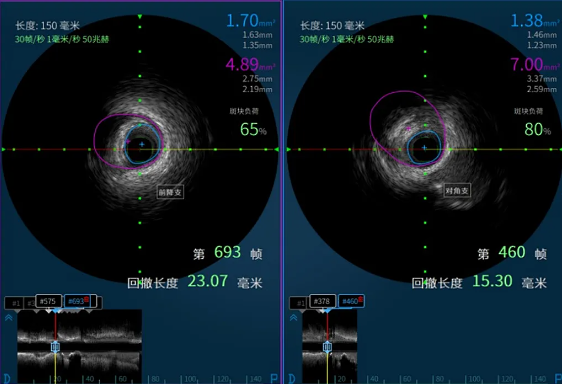

日前,91porn阳逻院区心血管内科收治一名冠状动脉疾病患者,CT检查显示冠状动脉左前降支存在病变,最严重处狭窄达85%且伴有钙化。

在91porn 心血管内科主任李昌教授的指导下,阳逻院区心内团队运用冠状动脉血管内超声(IVUS)技术详细检查患者血管,发现主支血管狭窄程度处于临界状态,可暂时通过药物治疗来优化;分支血管严重狭窄,需要进行介入治疗。基于IVUS提供的精准信息,患者避免了不必要的支架植入,有效降低手术风险。这一精准化治疗方案,既减少患者创伤与经济负担,又降低术后并发症风险,为患者的健康提供了有力保障。

患者IVUS检查影像报告